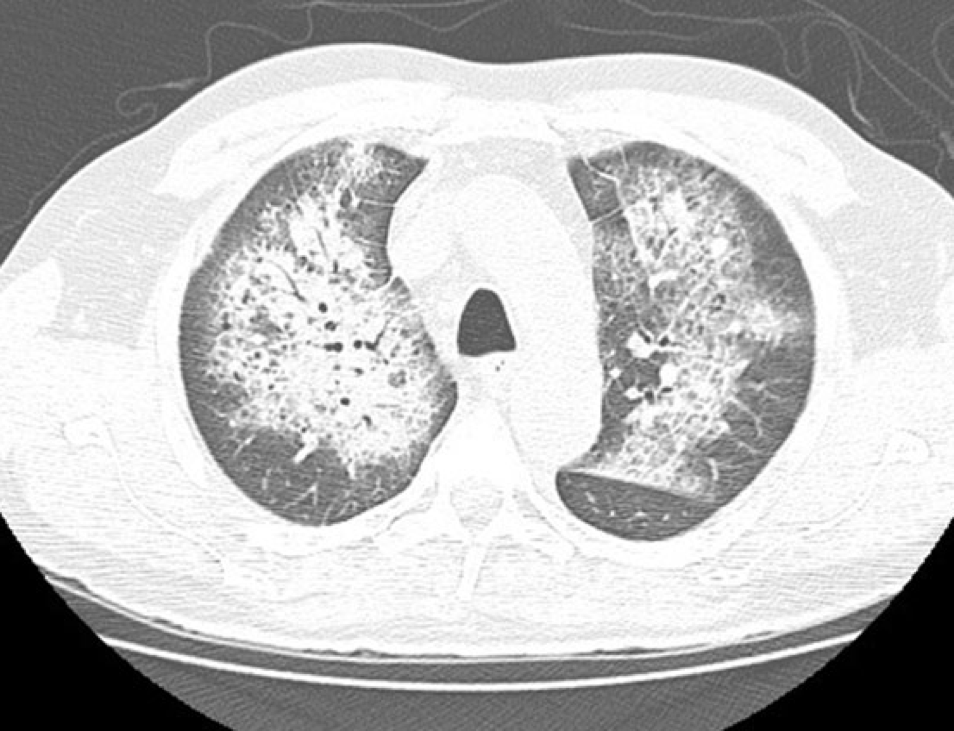

The patient’s hemoglobin dropped from 8.1 g/dL on admission to 6.4 g/dL and her oxygen requirements increased. She was eventually placed on high flow nasal cannula and developed acute hypoxemic respiratory failure requiring intubation and mechanical ventilation. Bronchoscopy visualized diffuse frank blood in both lungs consistent with diffuse alveolar hemorrhage. Anticoagulation was discontinued, and she was transfused packed red blood cells. Viral panel from the bronchoscopy was positive for rhinovirus. For the presumed diagnosis of diffuse alveolar hemorrhage, she was started on high dose steroids and continued on mechanical ventilation for airway protection.

Discussion: Acute hypoxemic respiratory failure is a common diagnosis encountered by hospitalists. Diffuse alveolar hemorrhage (DAH), although an infrequent cause of acute hypoxemic respiratory failure, cannot be missed. Typical features of DAH include hemoptysis with diffuse alveolar infiltrates on imaging. Interestingly, our patient did not experience hemoptysis.

Conclusions: Physicians must recognize that an atypical presentation for acute hypoxemic respiratory failure could be secondary to Diffuse Alveolar Hemorrhage. Typical features of DAH include respiratory compromise and hemoptysis with progressive alveolar infiltrates on chest imaging. Although DAH is most commonly caused by vasculitic and autoimmune disorders, it can occur secondary to medication side effects. Bronchoscopy is an important diagnostic modality in the setting of acute hypoxemic respiratory failure of unknown etiology.